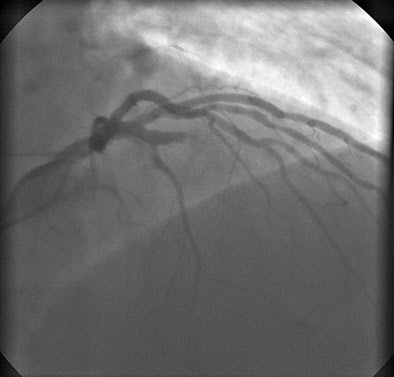

![]() |

| All images were acquired in a 62-year-old man presenting to the hospital for evaluation of chest pain. Left heart catheterization confirms occlusion of the mid-LAD. |